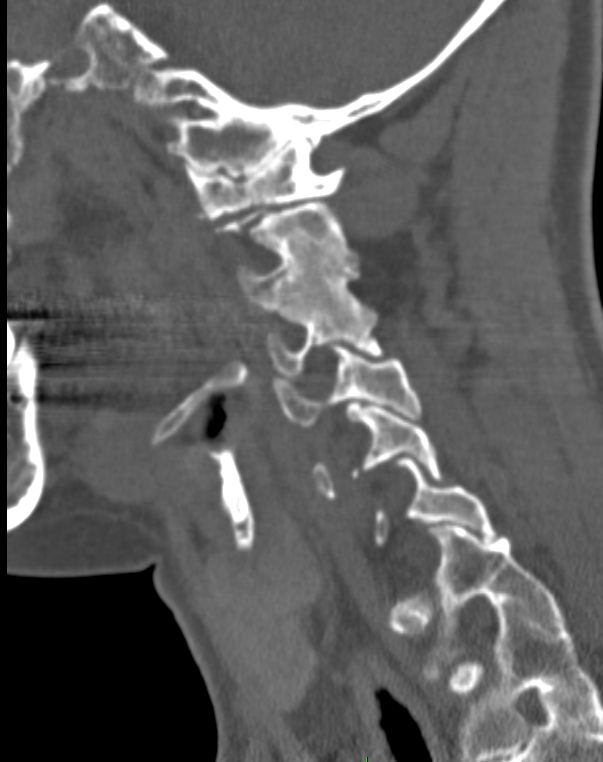

Sagittal CT shows extreme platybasia (NTB angle=180°), short clivus (<1.5 cm) and forward folding of the clivus–axis angle of Wackenheim (80°), causing lordotic tilt of the foramen magnum plane and plane of the occipital condyles, resulting in a retroflexed dens and severe basilar impression.

• Note violation of McGregor’s, Chamberlain’s and McRae’s lines by the dens. Also, extreme invagination of the opisthion (O) and high posterior C1 arch (C1).

• Sagittal MR shows distortion and compression of brainstem by both the dens and the opisthion